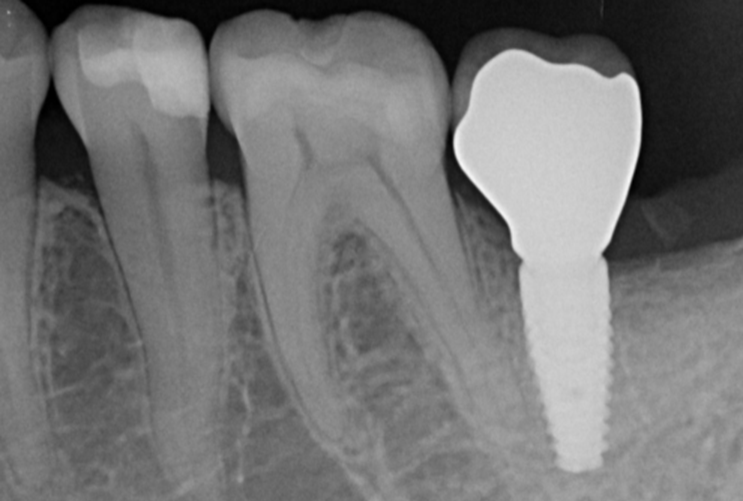

Pre-extraction images

5.Following a 6-month osseointegration period, the implant exhibited favorable bone integration, and the final crown was successfully delivered.